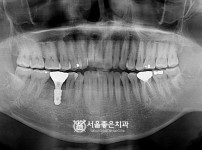

(수면+뼈이식) 임플란트 10개 - 오스템 임플란트 / 오래전에 하신 브릿지 흔들림 심하여 임플란트

해당 게시물은 의료법 제56조에 의거하여 로그인 후 열람이 가능합니다.

구분 임플란트